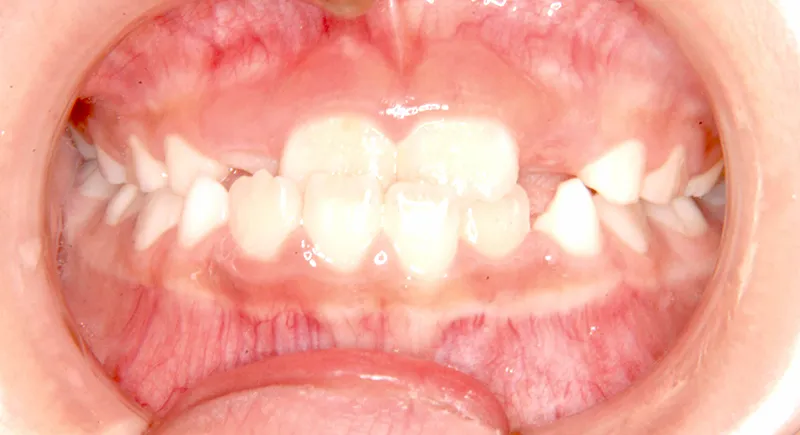

【子供の矯正(一期)】叢生・反対咬合・受け口・非抜歯症例・7歳女児【M.H様】

初診時年齢 小学校1年生 (女性) 主訴 受け口

診断名 叢生・反対咬合 装置名

状態 永久歯が生える隙間がない(叢生)

受け口(下顎前突/反対咬合)

下顎が大きい傾向があります。

上下の真ん中にズレがあるのと、上下とも永久歯の生えるスペースがせまいため、オリジナル矯正装置でスペースを作り、受け口も改善していきます。